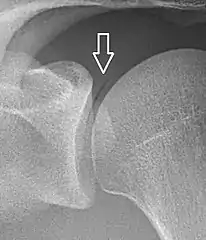

- A vacuum sign, or vacuum phenomenon, is a normal finding on shoulder X-rays.